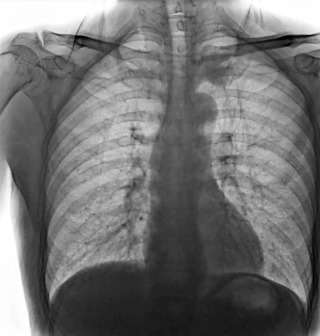

靜態(tài)DR受限于二維成像,在拍攝隱匿性病灶時(shí),由于組織重疊病灶難辨,耗費(fèi)時(shí)間更長(zhǎng)且易漏診、誤診。而動(dòng)態(tài)DR則具備實(shí)時(shí)動(dòng)態(tài)成像功能,可通過(guò)實(shí)時(shí)連續(xù)成像,對(duì)于重疊部位病灶或者易被遮擋的病灶進(jìn)行多角度動(dòng)態(tài)觀察,快速實(shí)現(xiàn)動(dòng)靜態(tài)轉(zhuǎn)換點(diǎn)片。